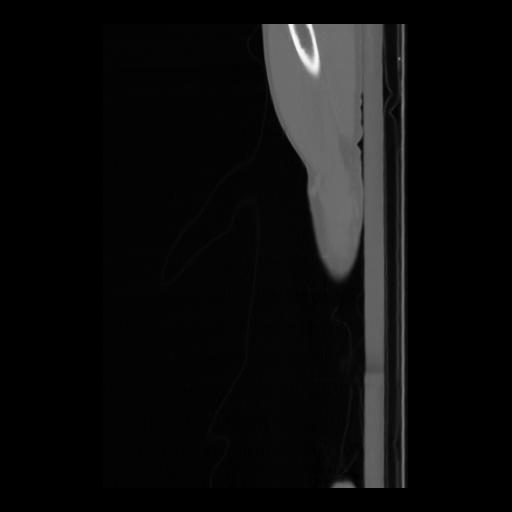

36 CUERPO,CE,Sagittal,3.000,CUERPO,Sagittal,